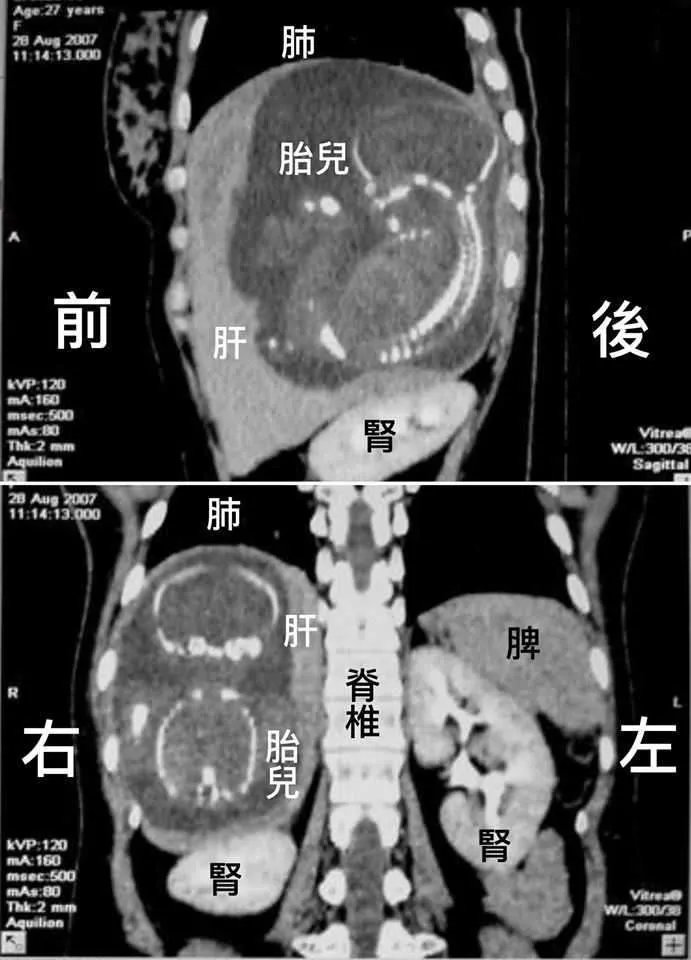

产检时发现胎儿长在肝脏里加拿大医生分享案例太罕见

妊娠发生在输卵管,极少数受精卵会掉到腹腔内进行着床,长在肝脏上的更

全球不足30例广西一女子怀孕胎儿却长在肝脏里能生下来吗